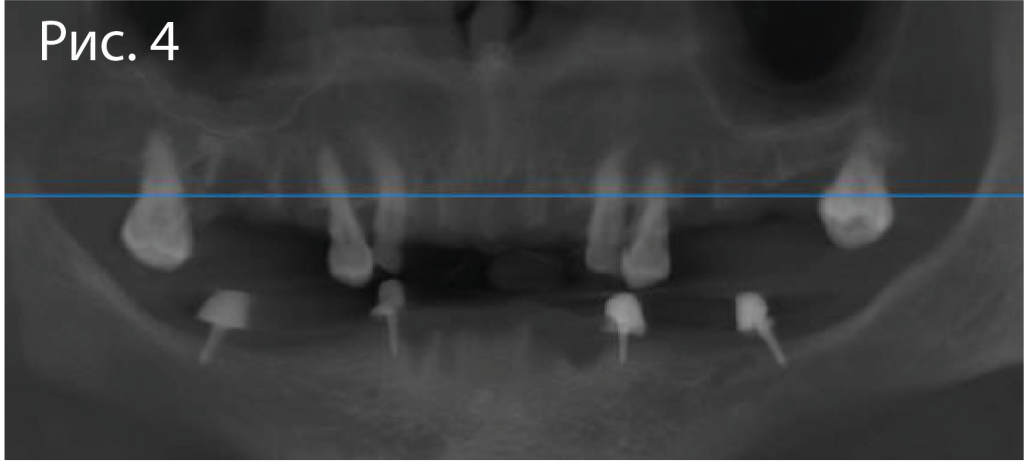

4.png

Данные интраорального сканирования и КТ сопоставляются в программе Implant Studio (3Shape). На верхней челюсти в качестве ориентира используются 6 зубов, на которые также будет опираться хирургический шаблон. На нижней челюсти с этой целью наносят текучий композит на шляпки ортодонтическоих винтов Osstem.